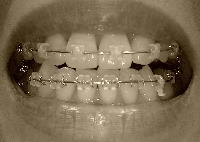

とうとう、全部の歯に装置が付いてから1年になりました!抜歯の隙間も埋まったし、ここまではいろいろあったけどほぼ順調だな~と思います(顔が元に戻ってきたので浮かれているw)もともと、ガタガタを整列させるのに1年、抜歯の隙間を埋めるのに1年、その後微調整で2~3ヶ月という予定だったらしいのです。まあ、微調整が予定以上にけっこうかかりそうではありますが…。先生に「前回歯を削ったけど、どうですか?変わりました?」と聞かれたので「はい、もうかなり劇的に変わったと思います。正直1.5ミリでどれだけ下がるんだろう?と半信半疑だったんですよ~」と答えました。先生はにっこり笑って「それはよかった。実は抜歯しても7ミリぐらいしか隙間は得られないので、1.5ミリっていうのはけっこう大きいんですよ」と言われました。下顎はゴム無しで、針金で固定に入りました。上顎は、アンバランスに大きい右2番(1番と同じぐらい大きい)を3番との隙間で0.5ミリ削って新たに隙間を作りました。そしてパワーチェーンで左右とも3番←→7番を引っ張って前歯を下げる方式。前回と同じです。前からはほとんど変化なくなりましたね。正中はあってないけど、最終的にも合わなくても…あんまり気になりません。そして、横からも撮ってみました比較写真。上の前歯、引っ込んでますよね?もう一息引っ込んでほしいけど、引っ込むってわかったから安心して治療を進められます。たまたま他に患者さんがいなくて、カウンターでちょっと先生と立ち話しました。「今日でちょうど装置が全部ついてから1年なんですよ~」「あ、そうなんですか!抜歯したにしては、やっぱりきたみんさん早いですよ」そして、付け加えて言われました。「お口の中はまだまだお若いってことですよ!」いや~そうですかね~ははは(ノ´∀`*)と笑って帰って来ましたが、そこはかとなく失礼なこと言われた気がする…(^-^;)ちなみに、先生は私より3歳年下なのでした。